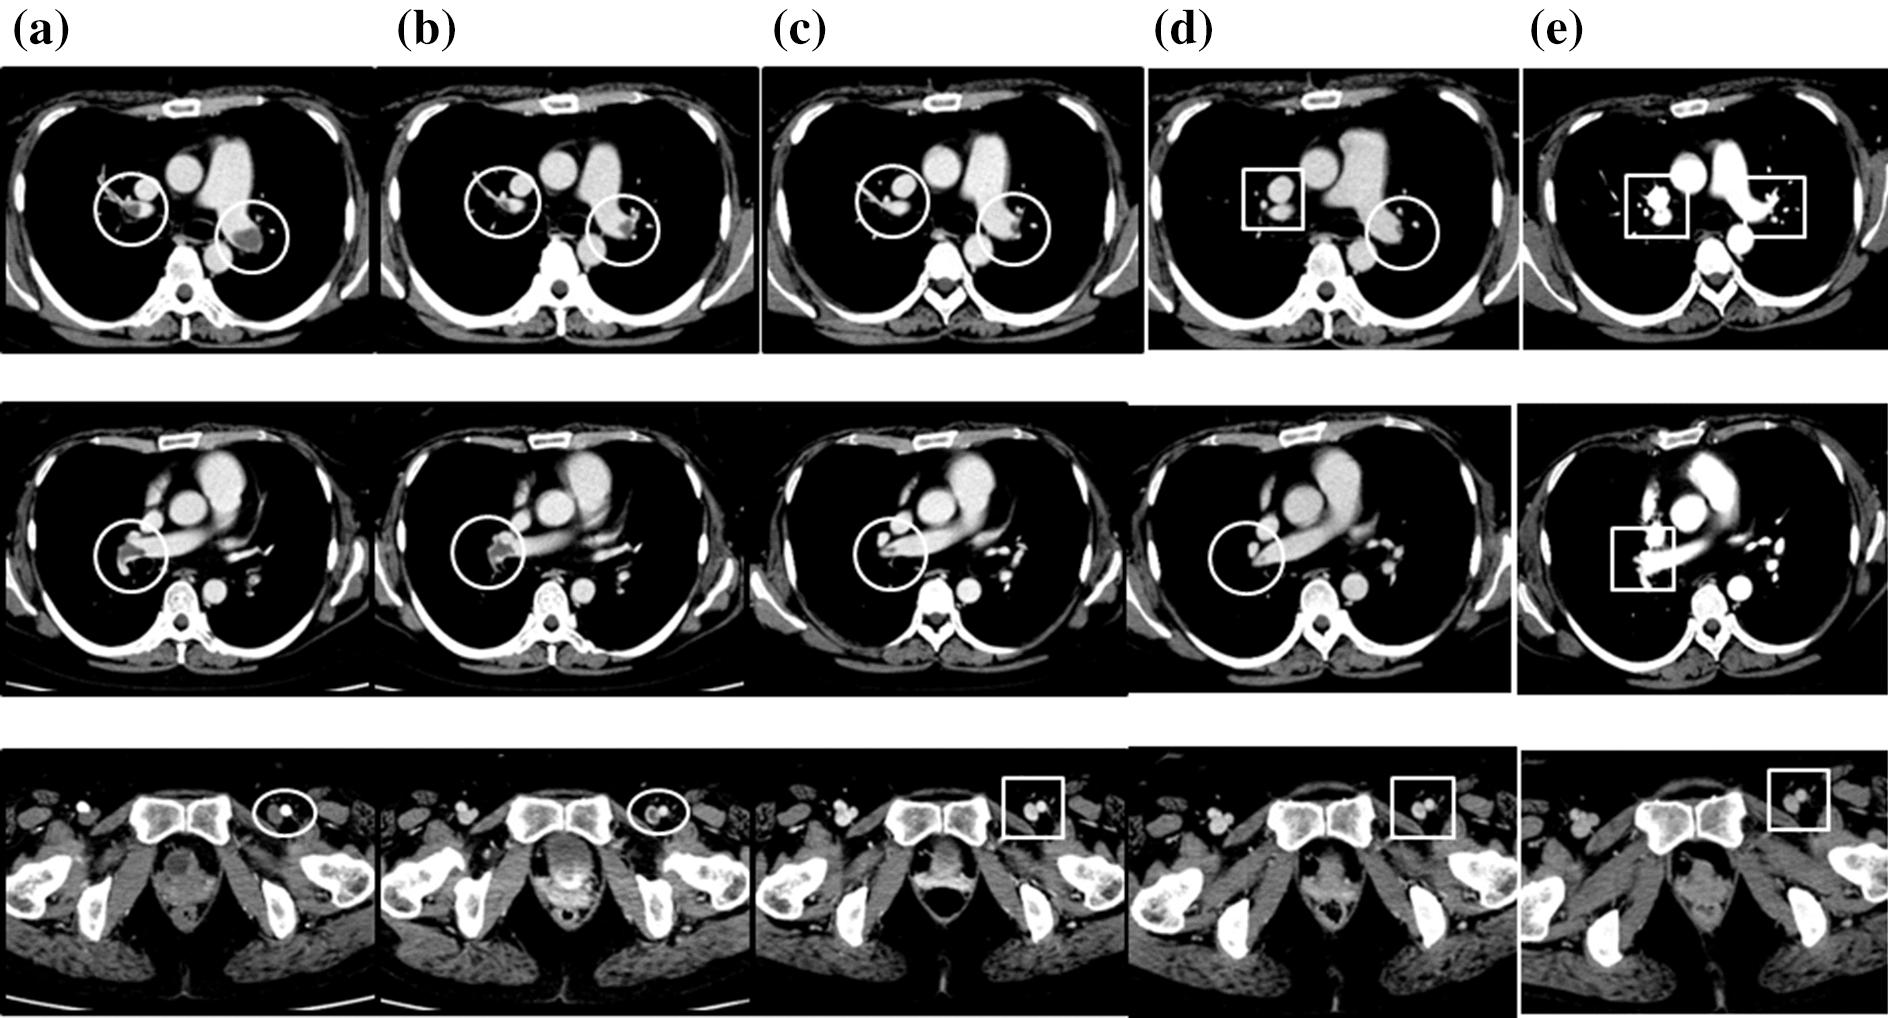

We report the case of a 43-year-old woman with eosinophilic granulomatosis with polyangiitis and acute respiratory and heart failure due to bilateral pulmonary artery thrombosis and left femoral vein thrombosis 12 years after disease onset. She also had cardiac involvement (myocarditis, pericardial effusion, and diastolic dysfunction), gastrointestinal symptoms, and peripheral neuropathy. The condition was refractory to treatment with systemic corticosteroids, intravenous cyclophosphamide, and mepolizumab, but the thrombosis and associated acute cardiac failure, as well as the cardiac and gastrointestinal symptoms and multiple polyneuropathy, improved after a switch to rituximab. However, the heart failure did not improve sufficiently and the patient continued to need inhaled oxygen at 1 L/min and asthma exacerbations occurred. We then swapped the patient's mepolizumab treatment for dupilumab. Not only did she have no further asthma attacks after switching to dupilumab, but also her vasculitis symptoms improved. Oxygen therapy was discontinued as the heart failure improved 5 months after starting the dupilumab.

我们报告了一例43岁女性,患有嗜酸性肉芽肿性多血管炎,在疾病发作12年后因双侧肺动脉血栓形成和左股静脉血栓形成出现急性呼吸和心力衰竭。她还存在心脏受累(心肌炎、心包积液和舒张功能障碍)、胃肠道症状和周围神经病变。该患者对全身用糖皮质激素、静脉注射环磷酰胺和美泊利单抗治疗无效,但在换用利妥昔单抗后,血栓形成及相关的急性心力衰竭、心脏和胃肠道症状以及多发性多发性神经病均有所改善。然而,心力衰竭改善不充分,患者仍需1L/min的吸氧,且哮喘发作。然后我们将患者的美泊利单抗治疗换为度普利尤单抗。换用度普利尤单抗后,她不仅没有再发生哮喘发作,而且血管炎症状也有所改善。开始使用度普利尤单抗5个月后,随着心力衰竭改善,停止了氧疗。